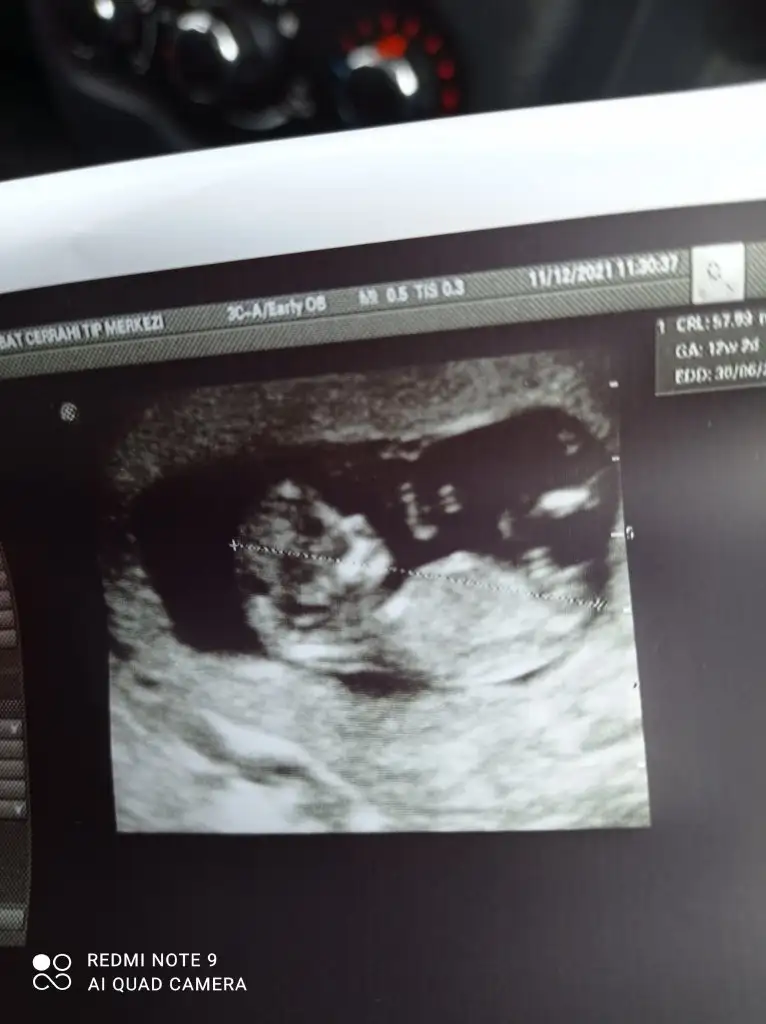

Şimdilik kız yönünde ama en iyi 11 12 13 haftalar olmalı

Benimkine de bakar misiniz arkadaşlarŞimdilik kız yönünde ama en iyi 11 12 13 haftalar olmalı

Erkek ve kız için 11 + 12+ yada 13 hafta usg görüntüsü olmalı açıklamalar asagıda yazıyorrabbim herkesin gönlüne göre nasip etsin inşallah .. ecmain

[/B]Eki Görüntüle 473828 gordugunuz gibi ust taraftaki simgedende anlasildigi gibi eger cikinti paralel ise kiz

yok 30°lik bir aciyla yukari dogru bakiyorsa %99 oglunuz olacak demektir simdi bi kac ornek resimler daha koyacagim kiziminkide dahil

Eki Görüntüle 473831 simdi burada cikintilara bakin eger bel popo cizgisine paralel ise kiz

yok 30 derecelik bir aciyla yukari bakiyorsa erkek

bence erkek canımMerhaba daha öncede sormuştum belli değil demiştiniz şimdi 14 haftalık doktor yüzde 50 kız dedi sizce ne